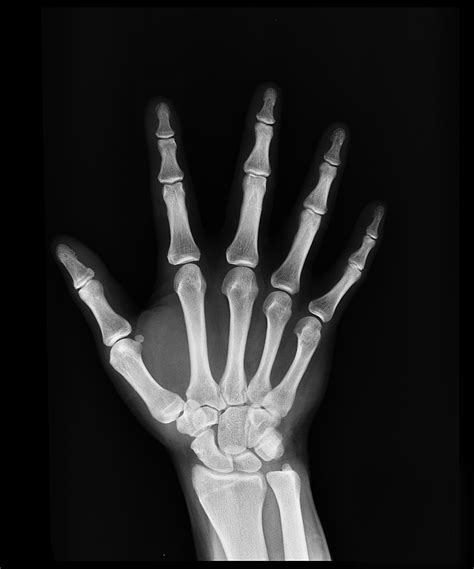

In the realm of medical diagnostics, the Hand X Ray stands as a cornerstone tool, providing invaluable insights into the skeletal structure and soft tissues of the hand. This non-invasive imaging technique has revolutionized the way medical professionals diagnose and treat a wide range of conditions, from fractures and dislocations to arthritis and tumors. Understanding the intricacies of Hand X Ray imaging is crucial for both healthcare providers and patients alike.

A Hand X Ray is a type of radiography that uses electromagnetic radiation to produce images of the internal structures of the hand. This process involves passing X-rays through the hand and capturing the resulting image on a detector. The varying densities of different tissues—such as bone, muscle, and fat—absorb the X-rays differently, creating a contrast that allows for detailed visualization.

• hand x ray anatomy labeled

• normal hand x ray